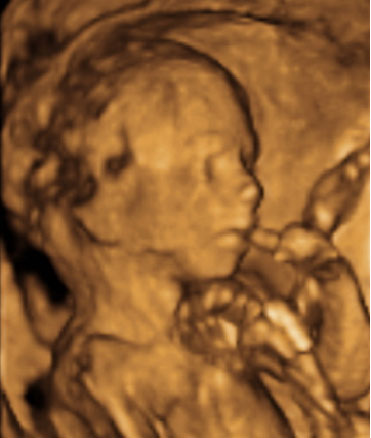

En la 20 semana de gestación, los órganos sexuales del feto, masculinos o femeninos, ya están formados y son visibles, especialmente con una ecografía en 4D. Aquí la imagen ha captado el sexo de un niño.

Ecografía semana 20: sexo masculino

En la imagen podemos ver un feto de 20 semanas y 6 días de gestación del sexo masculino.